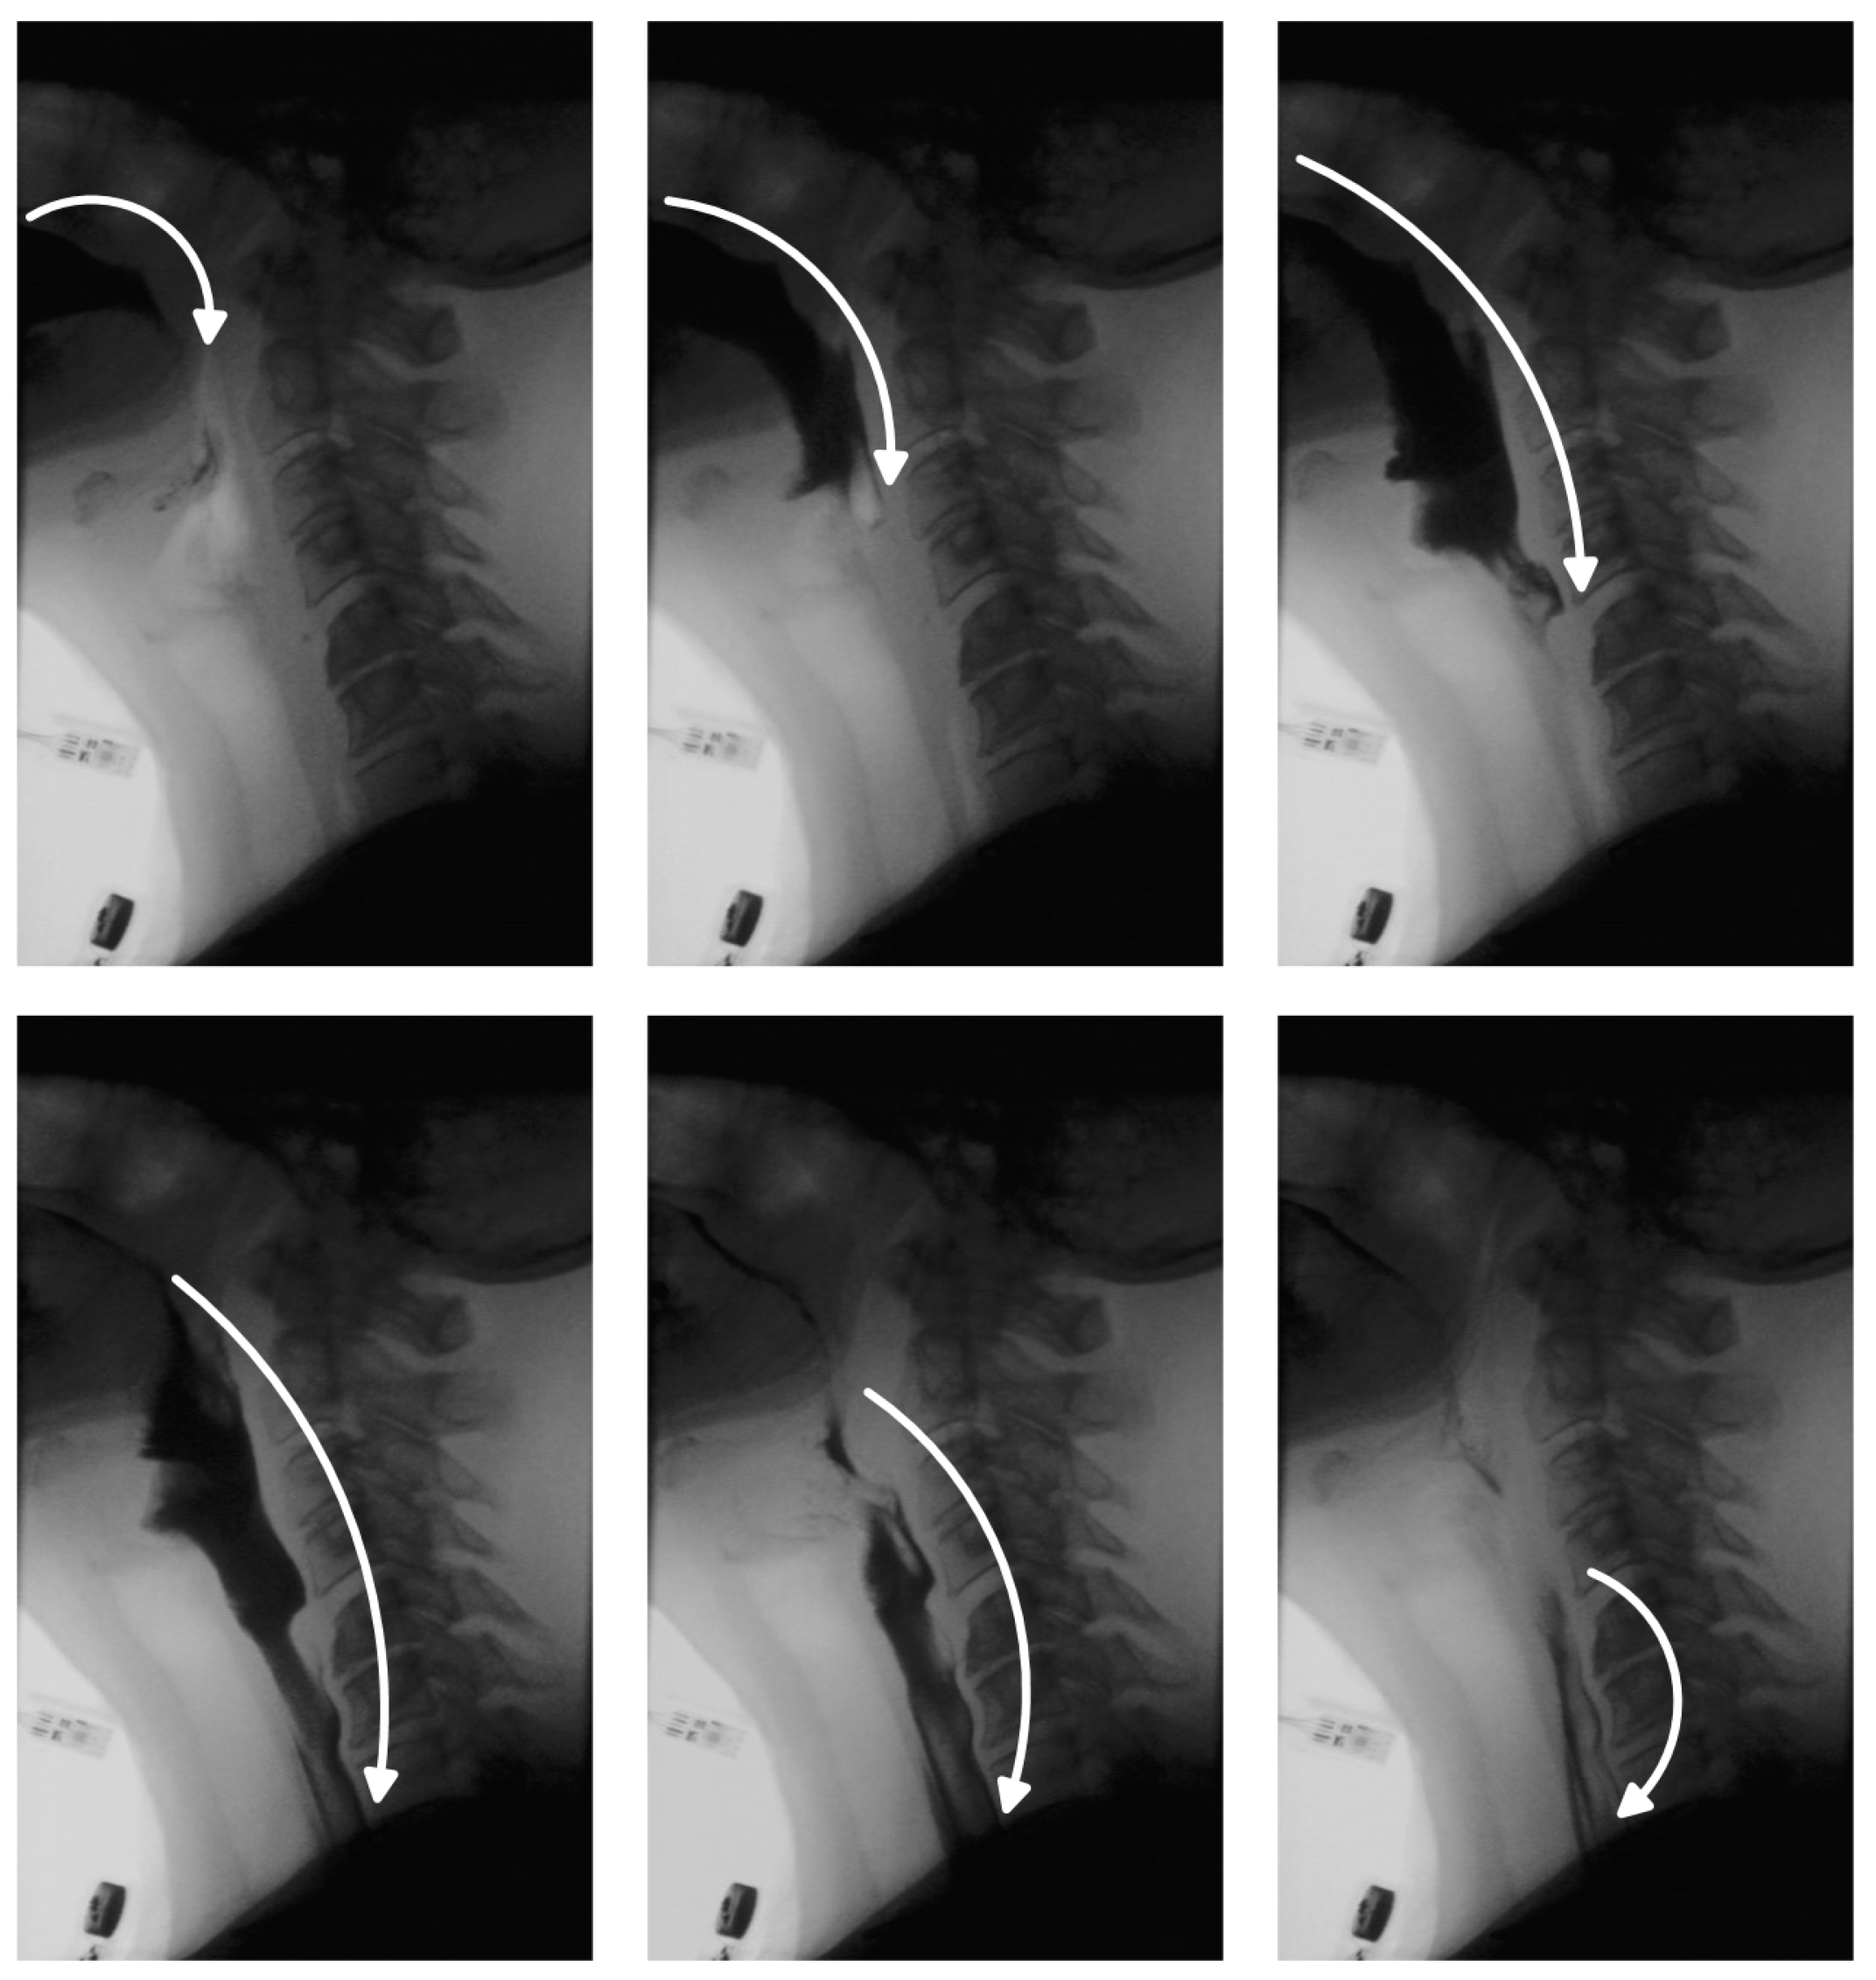

One of the critical aspects of VFSS analysis is bolus tracking, which enables clinicians to assess the safety and efficiency of swallowing [9]. In a healthy swallow, the bolus moves smoothly and continuously from the oral cavity to the esophagus and into the stomach (Figure 1). In individuals with swallowing disorders, however, this movement may deviate from the normal trajectory, leading to complications. The bolus may be misdirected into the nasal cavity, fragment into smaller portions swallowed sequentially, or enter the pharynx while the airway is unprotected—raising the risk of aspiration pneumonia. In other cases, part of the bolus may remain in the oral or pharyngeal region, resulting in residue that can cause postprandial choking. While residue detection is as clinically important as bolus tracking, it has received comparatively less attention in research due to the inherent challenges in identifying small, low-contrast regions within complex anatomical backgrounds. Traditionally, clinicians manually review VFSS recordings, examining key frames to track bolus movement and identify residue. This process is time-consuming, susceptible to observer fatigue and variability, and requires specialized expertise, limiting scalability. Automated bolus tracking systems offer a promising alternative, providing more standardized and objective assessments. In addition to reducing manual workload, they facilitate quantification of important swallowing parameters, such as bolus transit time, penetration, and aspiration events.

Figure 1. Representative VFSS frames illustrating the progression of the bolus through the oral, pharyngeal, and esophageal phases of swallowing.